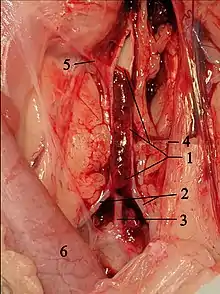

Saddle thrombus in the feline aorta. 1 opened Aorta with thrombus, 2 A. iliaca externa, 3 common trunk for both Aa. iliacae internae, 4 A. circumflexa ilium profunda, 5 A. mesenterica caudalis, 6 Colon descendens.

Feline arterial thromboembolism (FATE) is a relatively common and devastating complication of feline HCM and other feline cardiomyopathies. The thrombus generally forms in the left atrium, most commonly the left auricle. The formation is thought to be primarily due to blood flow stasis. Classically, the thromboembolism lodges at the iliac trifurcation of the aorta, occluding either one or both of the common iliac arteries. Because this split is called the saddle, and is the most frequent location for the thrombus, FATE is commonly known as saddle thrombus.[89] Clinically this presents as a cat with complete loss of function in one or both hind limbs. The hind limbs are cold and the cat is in considerable pain. Emboli may, rarely, lodge in other locations, most commonly the right front limb and the renal arteries.